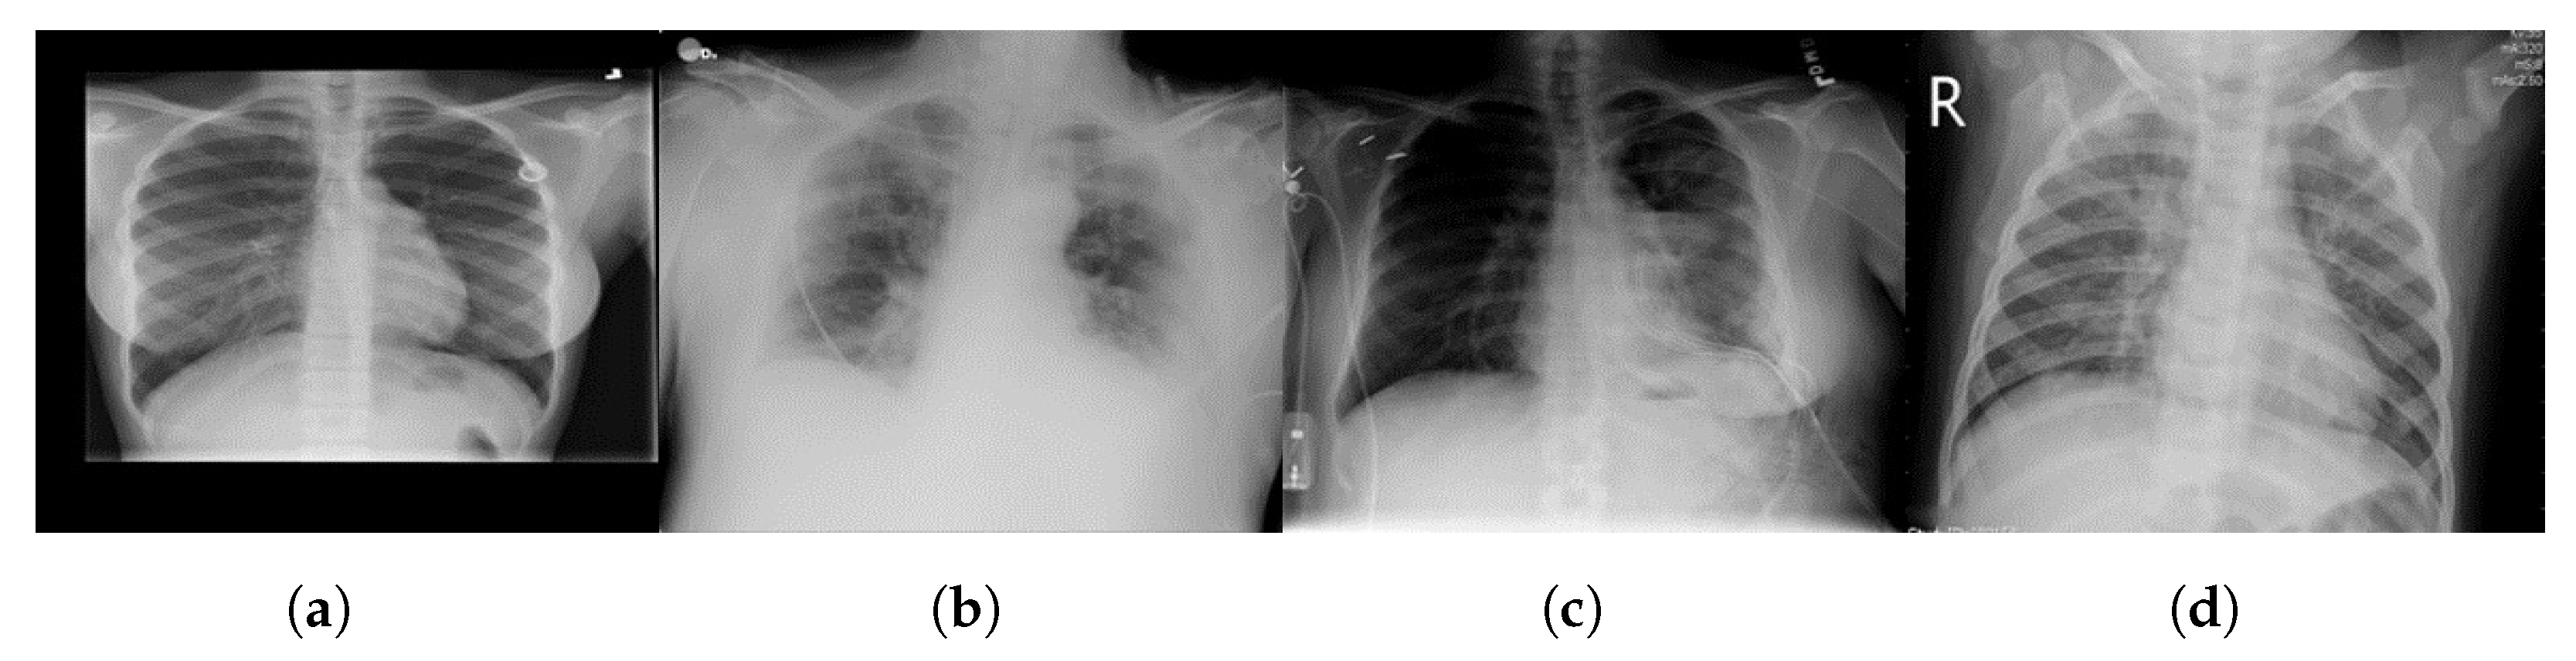

3.1.2. Chest X-ray (COVID-19) Dataset [82]

3.1.3. Ground-Truth Annotations

3.2. Dataset Preprocessing

3.2.1. Image Conversion to 8-bit

3.2.2. Grayscaling

3.2.3. Image Enhancement with Histogram Equalization (HE)

3.2.4. Image Adjustment